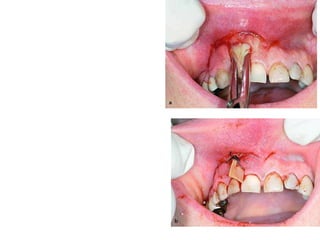

D- Treat surgically

 Extirpation of the necrotic tooth pulp

 Soft tissue incision

Establishment of Drainage

D- Treat surgically Extirpation of the necrotic tooth pulp  Soft tissue incision

• #65 Surgical treatment may range from something as simple as the opening of a tooth and extirpation of the necrotic tooth pulp to treatment as complex as the wide incision of soft tissue in the sub-mandibular and neck regions for a severe infection.